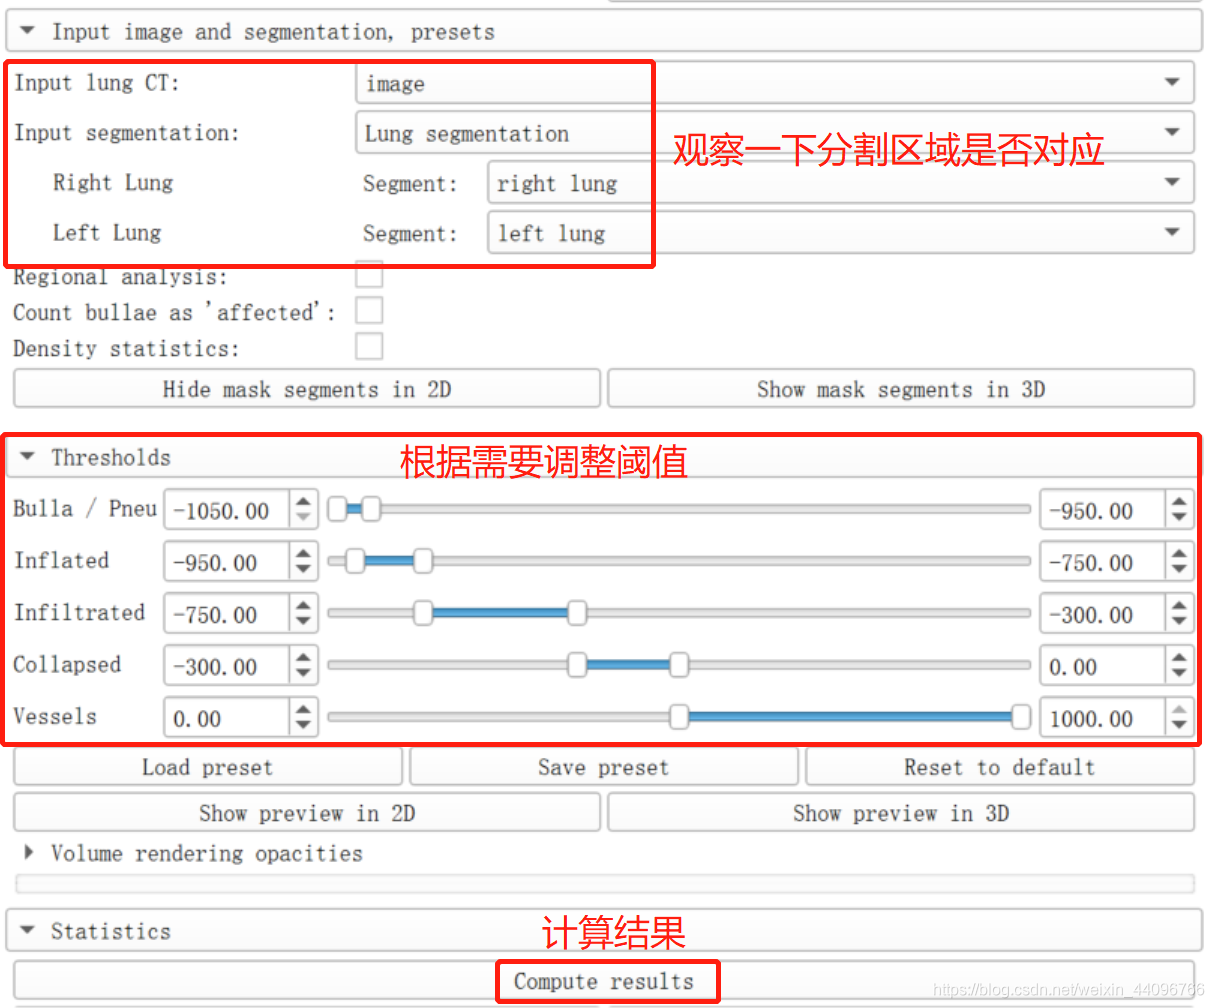

测量容积

- 进入插件

此处会弹出Error,直接点击ok即可。 - 设定阈值

阈值分割出肺大泡等病灶。

- 结果表

可以根据需要将表用不同格式导出。

注意:表中 Affected = Infiltrated + Collapsed

- show preview in 3D 查看3d效果